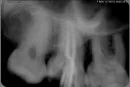

Все началось с того, что месяц назад у меня откололся кусочек зуба, на верхней челюсти 7-ка справа. При осмотре врач увидела кариес еще и на 8-ке и сказала, что из-за трудного доступа этот зуб лечить невозможно, нужно удалять, но пока зуб не беспокоит. Стали лечить отломанную 7-ку, удалили нервы. Положили на неделю лекарство. На следующем приеме мне закрыли каналы гуттаперчей и поставили временную пломбу. Никакого дискомфорта и боли я не чувствовала.

Прошло еще пару дней, и я стала замечать, что 7-ка стала реагировать на холод. Достаточно выйти на улицу, как зуб тут же начинает болеть, потом постепенно боль проходит. Я опять обратилась с этой жалобой к стоматологу. При осмотре врач предположила, что болит скорее всего 8-ка и отдает на 7-ку, т.к. в депульпированном зубе не может быть боли и реакции на холод. Но по моим ощущениям болит именно 7-ка.

Восьмёрка действительно проблемная и лечить её особо нет большого смысла. В связи с десневым карманом между этими зубами, на восьмом зубе проглядывается глубокая полость, что скорее всего и есть причина Вашей боли. Также верхушки каналов седьмого зуба плохо видны, но на мой взгляд наблюдается небольшое изменение.